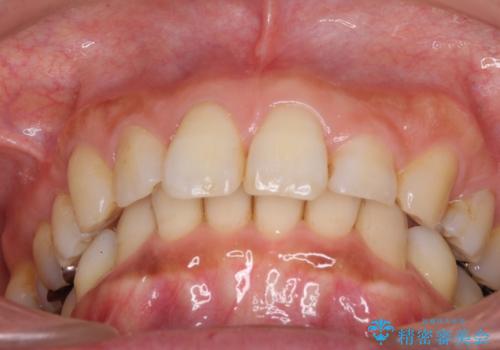

- 以前行った抜歯矯正が後戻りし、開いてしまったスペースが気になるとのことで来院された患者様です。

インビザラインを用いて開いてしまったスペースと前歯のデコボコを改善することとしました。

矯正治療後には気になっていた銀歯をセラミッククラウンやセラミックインレーにて治療することとしました。

上顎前歯を左右対称となるように歯列を整えたいとのことでしたが、すり減って形態が大きく異なっていたため、できる範囲での仕上がりとなりました。